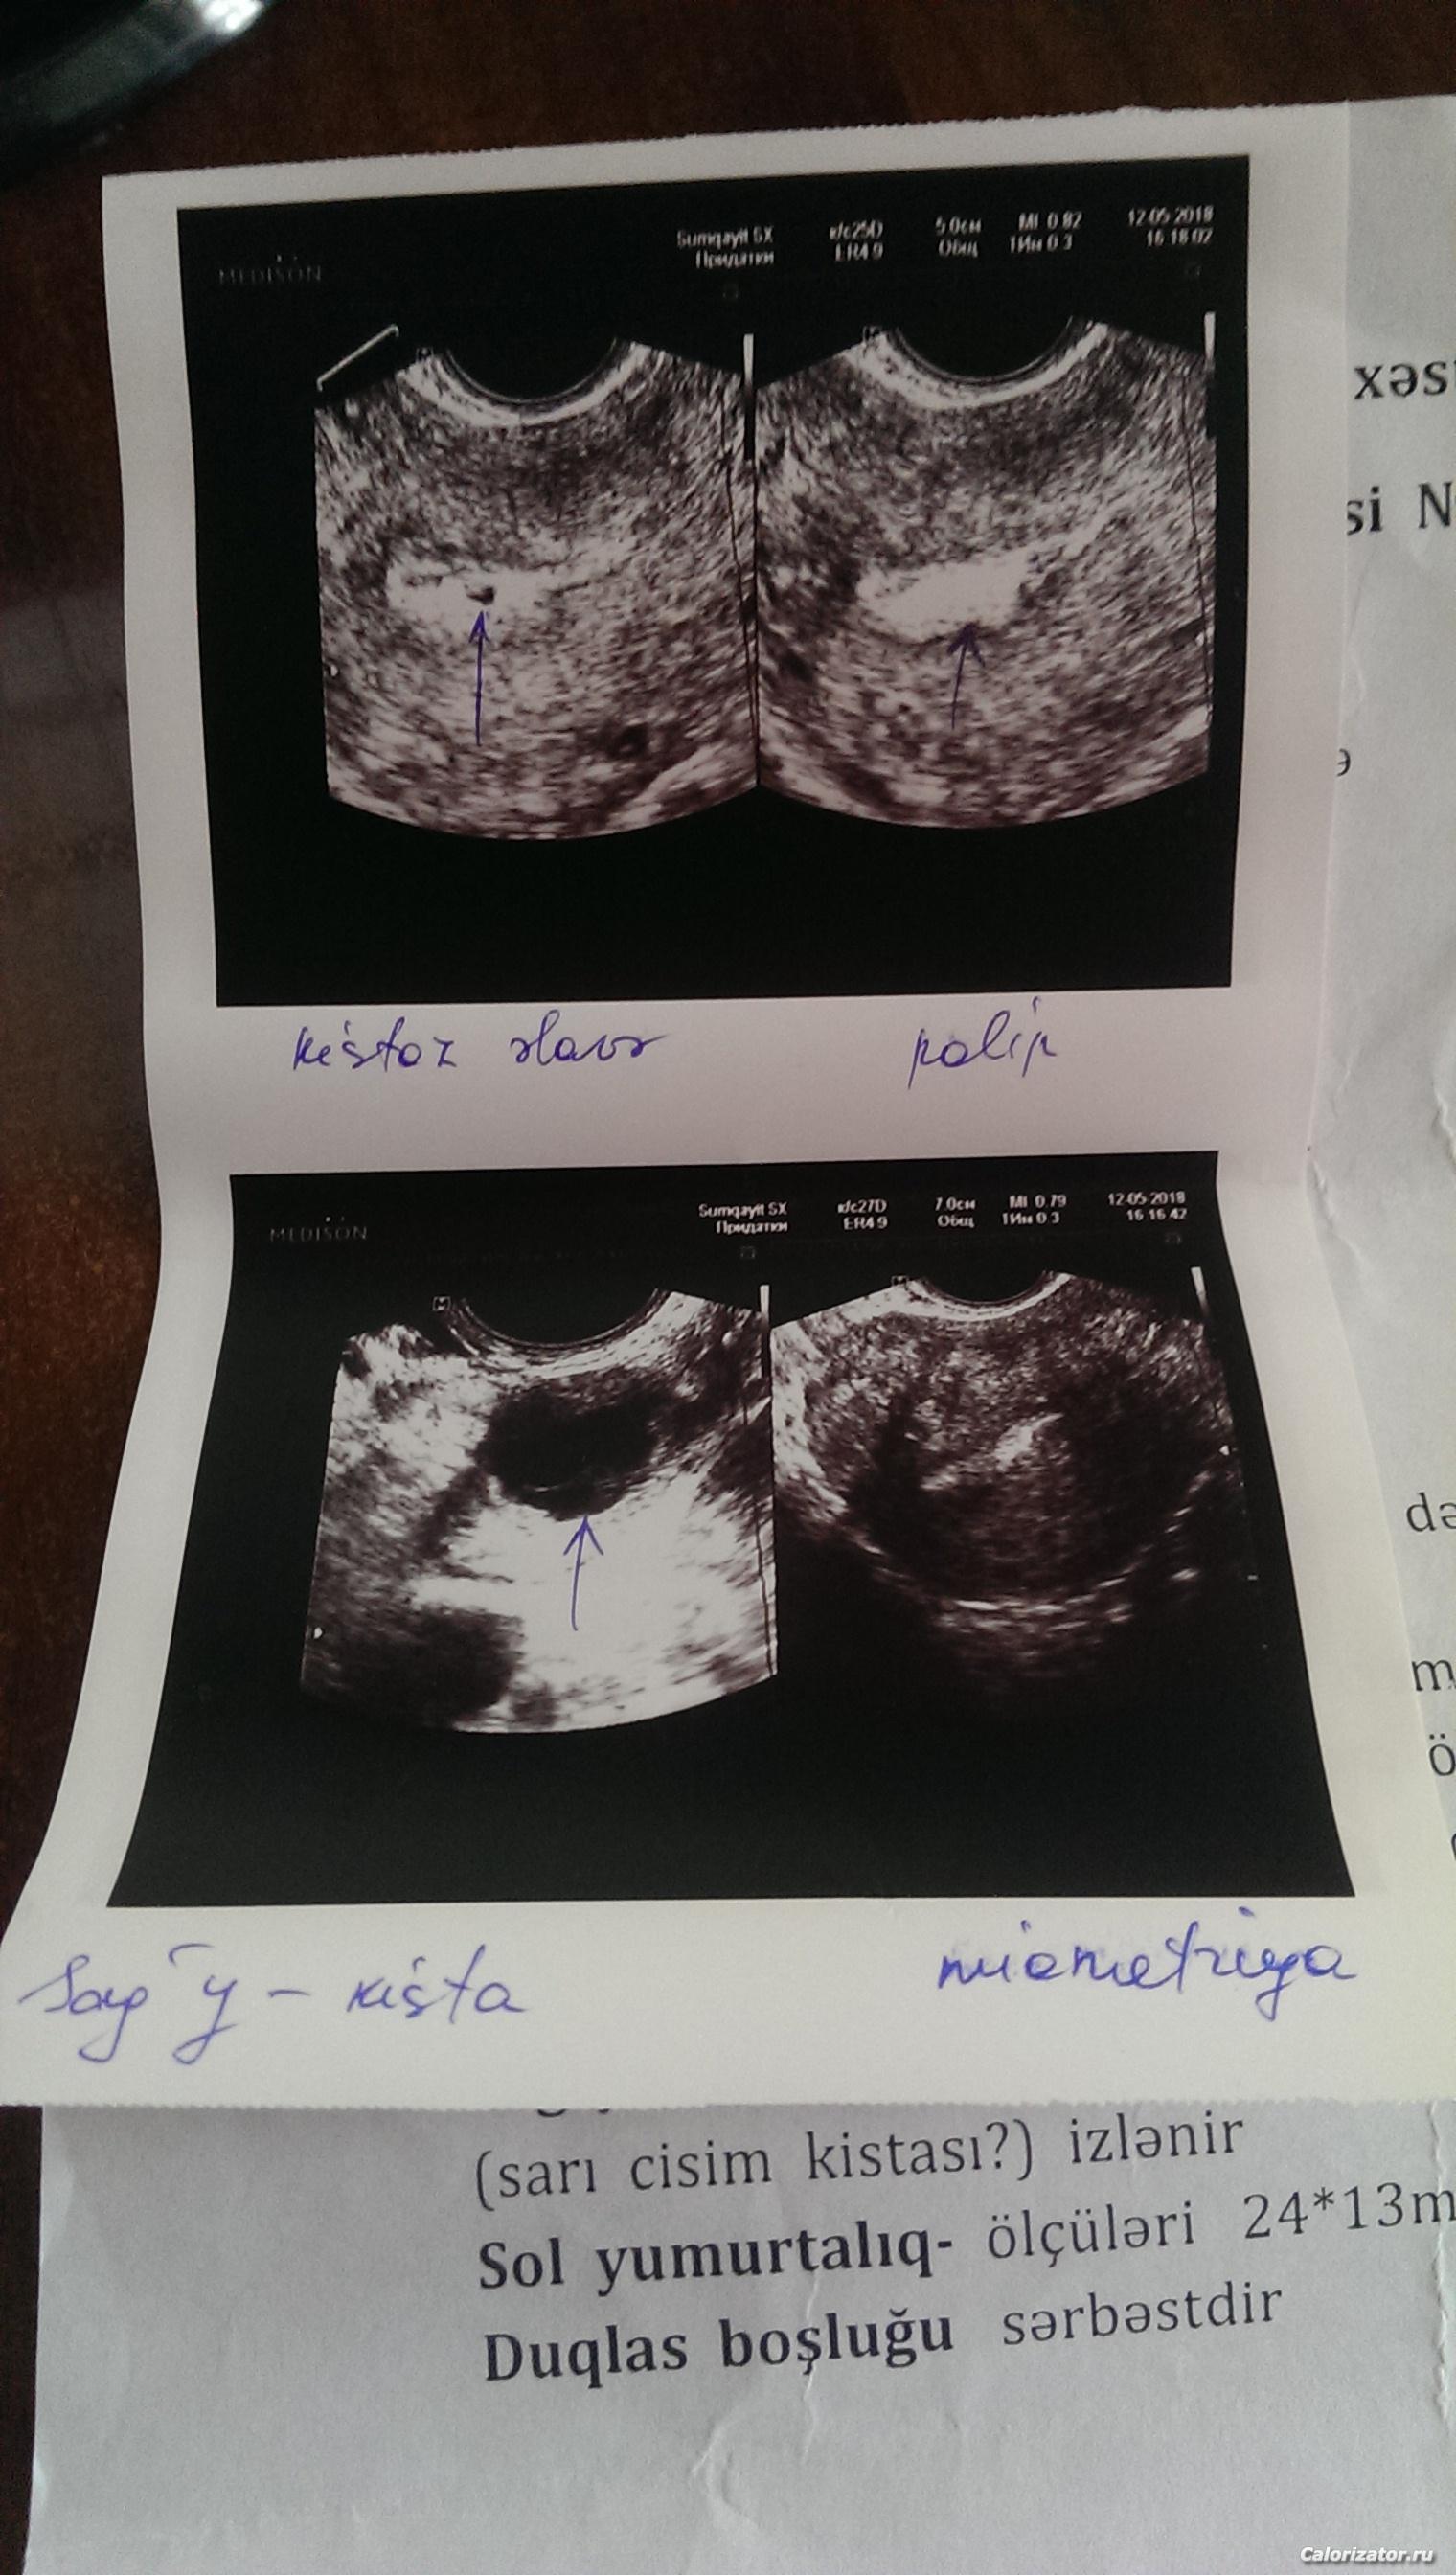

Свет описание есть ,но оно на азербайджанском языке.Попытаюсь перевести.Но для начала просто выставлю фотку и потом попытаюсь перевести.

6673266731

Свет итак.Жирным шрифтом мои комменты.Ну перевела как смогла)

Миометрия мелкозернистая.В лёгкой степени внутренний диффуз эндометриоз.

Эндометрий 7 мм,трёхслойная, на теле в размерах 4*2 кистоз, дополнение кистоз полип.Точный диагноз при след.месячных .

Правый яичник 32*18,17*14 наблюдается твёрдожидкостная киста?(не точно там вопрос).

Левый яичник 24*13 ,фолликулярный аппарат слабый([b]вообще на узи она еле увидела левый яичник)[/b]